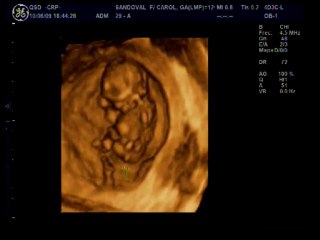

Dissection de l'aorte

Dédoublement de la paroi aortique chez un br Homme de 60 ans br Grand tabagique